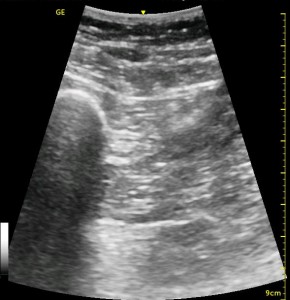

The following ultrasound image shows typical relationships of the sonoanatomy of the anterior sciatic nerve block. The femur is at 4cm on the right (lateral) of the image seen as a bright white horizontal line. Typically, there is a bone shadow below it, though there is some artifact below the femur here. The femoral vessels are seen between the 2cm and 3cm marks just to the right of center as a darkened area. They really can be determined by pausing for the appearance of arterial pulsation and venous compressibility. The adductors are seen to the left of the femur as a darkened area. Just deep to this between the 6cm and 7cm mark is a brightened rectangular shape, the sciatic nerve. The brightness fill fade with rocking of the probe over it. The nerve can be approached from the medial or lateral aspect of the probe, and moving the probe medially will sometimes allow for a better trajectory.

The image above is not an obvious one, and I did that on purpose. You have to get used to the idea that you will not always have a ‘super distinct’ image with this approach, and you will often need to use a number of additional clues to find your target and then to put local around it. I think the only way to really get a handle on being able to identify the basic elements is to look at several images over and over, so I have provided several below for you to use for practice. Note that the sciatic nerve will ‘poke out’ from behind the femur to different degrees depending on your orientation to the femur as well as to how far up or down the femur you go. It will be seen more if you are proximal. See how well you can identify the structures in the images below.